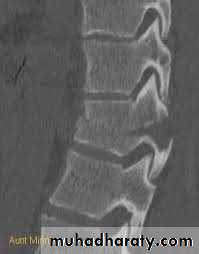

CT: best for bony anatomy.

Wedge fracture

Burst fracture

Chance fracture